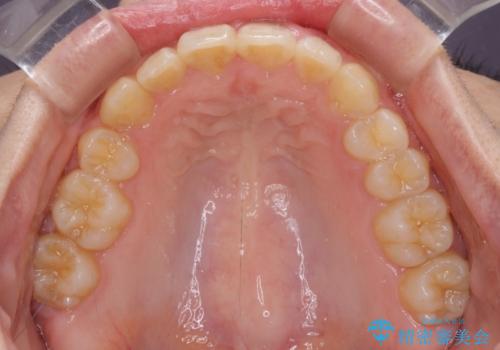

- 八重歯を気にして来院された患者様です。

八重歯の後ろの歯を1歯抜歯し、補助装置(リンガルアーチ)を用いて八重歯の位置を改善し、その後インビザラインにより矯正治療を行うこととしました。

下顎前歯が1本欠損したスリーインサイザーという状態であるため、上下の前歯の咬み込みが深くなったり、奥歯の咬み合わせが理想的なものとならなかったりという仕上がりになってしまいます。

前歯の見た目や奥歯の咬み合わせに、患者様が違和感を感じない状態として治療を終えました。